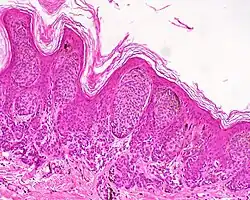

| Dysplastic nevus | Usually a compound nevus with cellular and architectural dysplasia. Like typical moles, dysplastic nevi can be flat or raised. While they vary in size, dysplastic nevi are typically larger than normal moles and tend to have irregular borders and irregular coloration. Hence, they resemble melanoma, appear worrisome, and are often removed to clarify the diagnosis. Dysplastic nevi are markers of risk when they are numerous, such as in people with dysplastic nevus syndrome. According to the National Institute of Health (NIH), doctors believe that, when part of a series or syndrome of multiple moles, dysplastic nevi are more likely than ordinary moles to develop into the most virulent type of skin cancer called melanoma.[19] | ![]() In this case, the central portion is a complex papule, and the periphery is macular, irregular, indistinct and slightly pink. |

Characteristic rete ridge bridging, shouldering, and lamellar fibrosis. H&E stain.